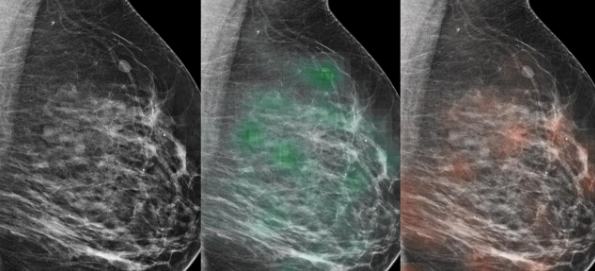

此外,研究人員設計了AI研究模型,首先要考慮全分辨率圖像的很小部分,以創(chuàng )建熱圖,即疾病可能性的統計圖。然后,程序會(huì )考慮整個(gè)乳房的與癌癥相關(guān)的結構特征,并更加注意像素級熱圖中標記的區域。